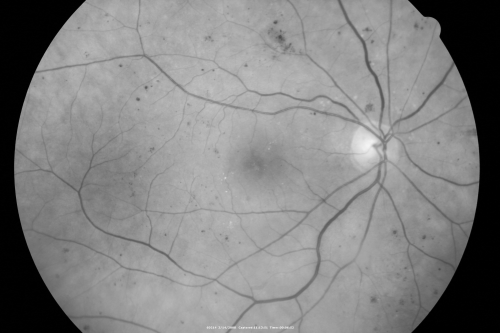

Diabetic Macular Edema Left Eye - Pre Laser

82-year-old woman diabetic for many years, last eye exam 5 years ago with gradual vision loss. OD 20/60, OS 20/70. IOP: OD 16, OS 17.